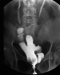

Abbildung 2: Blasentumor

Die frühpostoperative intravesikale Chemotherapie reduziert die Rezidivrate. |